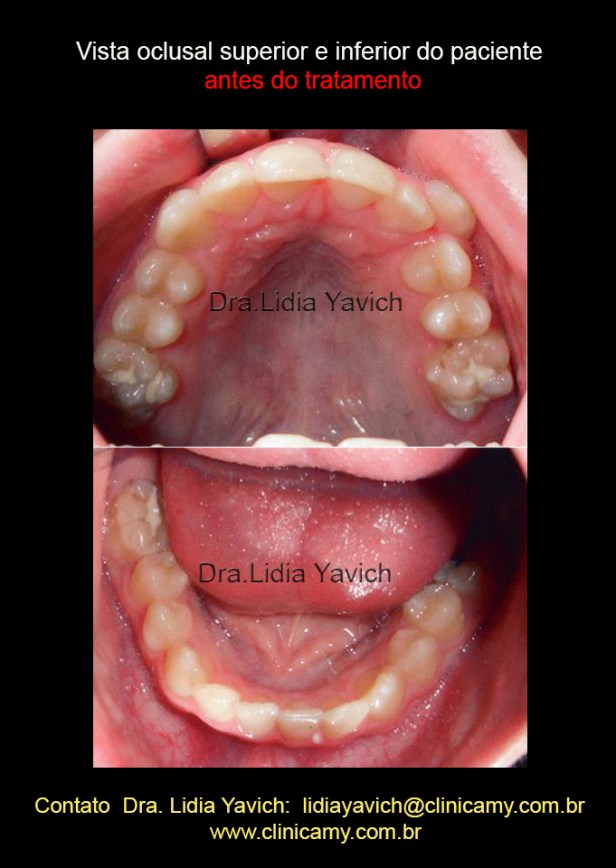

Vista oclusal superior e inferior do paciente antes de tratamento. Fica evidente a falta de espaço para o correto posicionamento do canino superior do lado esquerdo.